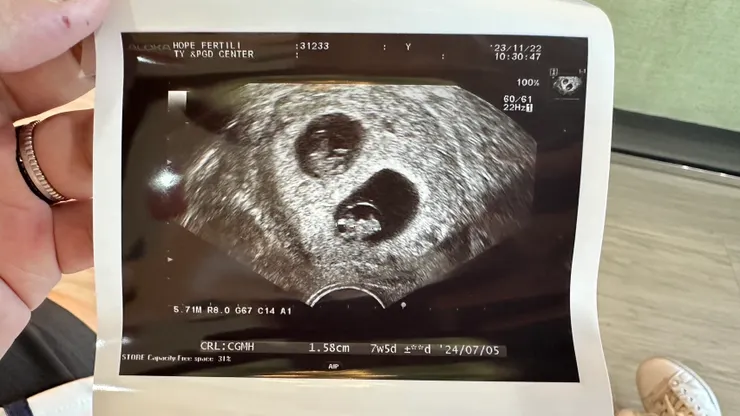

隔天,我們安排了回祈新做落地後的檢查,確認一下寶寶的狀況

長好大了唷!!!

因為週數的關係,所以這次還是使用陰道超音波的方式檢查

- A寶-7w5d、1.58cm、164 BPM

- B寶-7w4d、1.46cm、166 BPM

兩個小朋友的都長得非常不錯唷!我們也就安心了,但沒想到...才剛剛放心而已,卻又開始進入另一個緊張時刻...